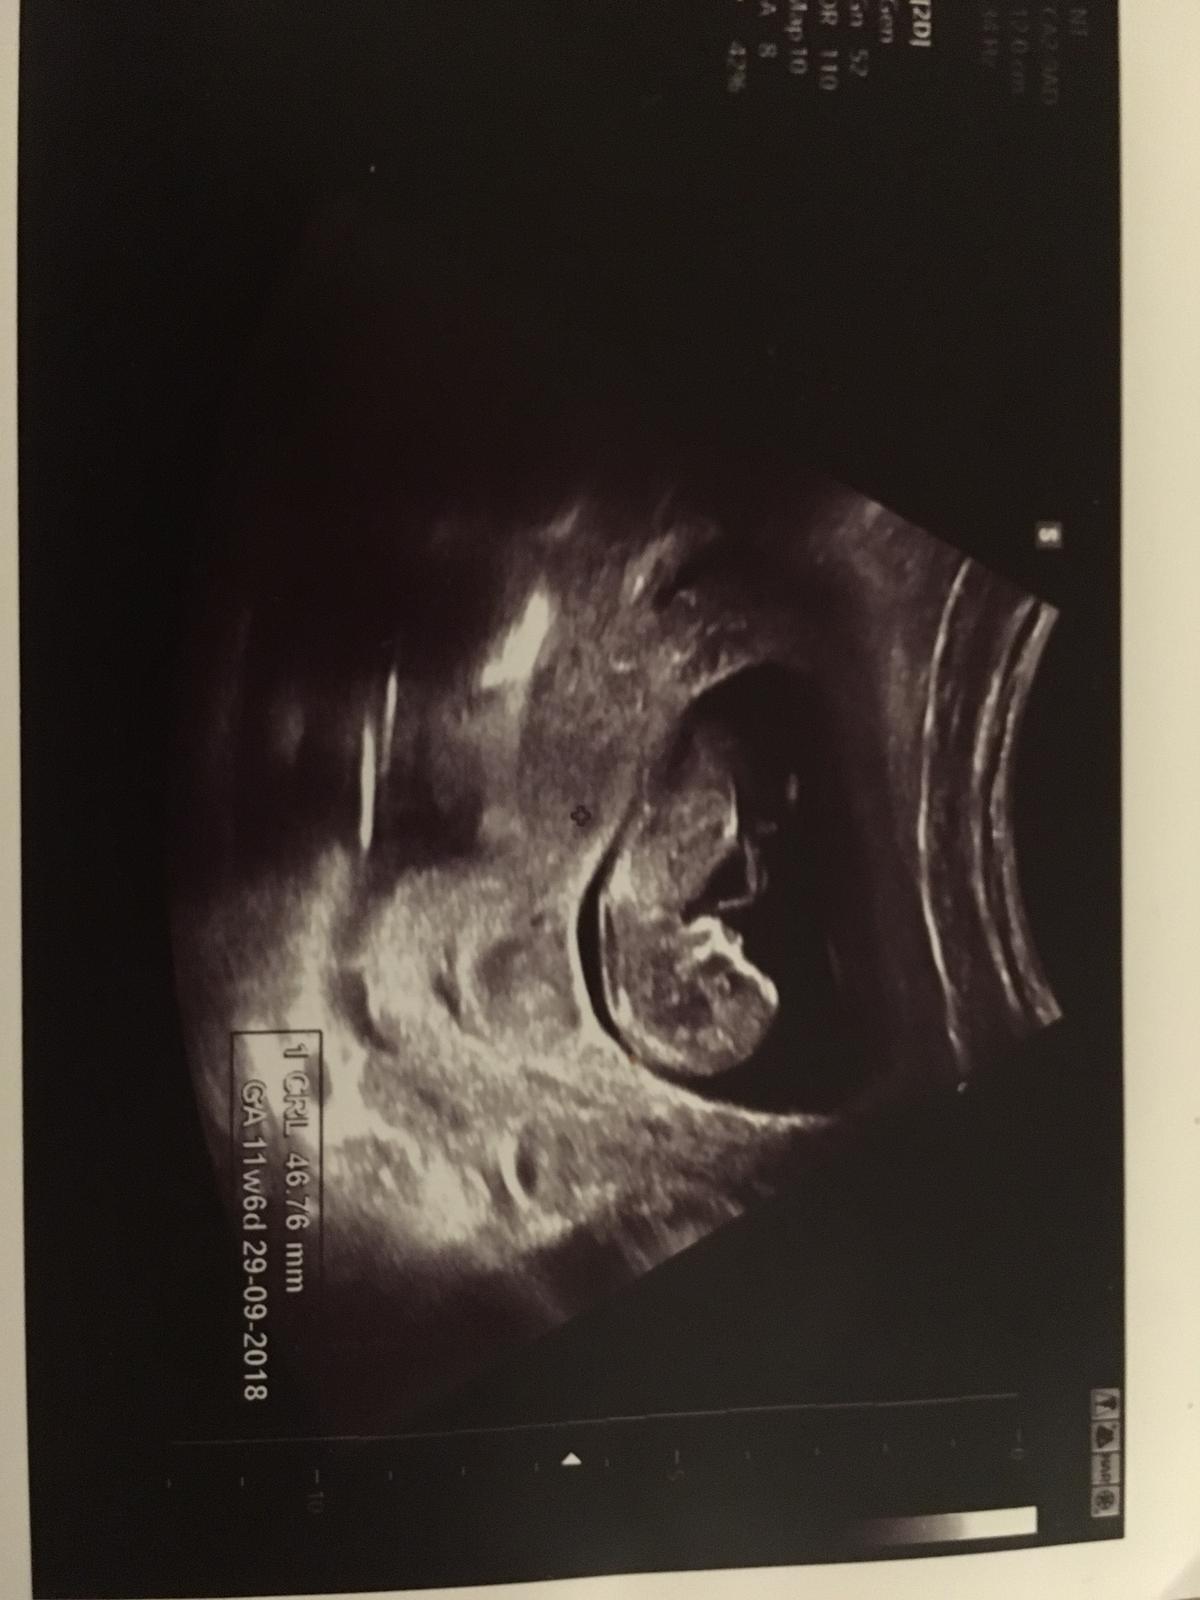

Holky, tak my máme po prvním screeningu. Co to bude zatím nevíme a fazolka je díky Bohu zdravá 👍🙏